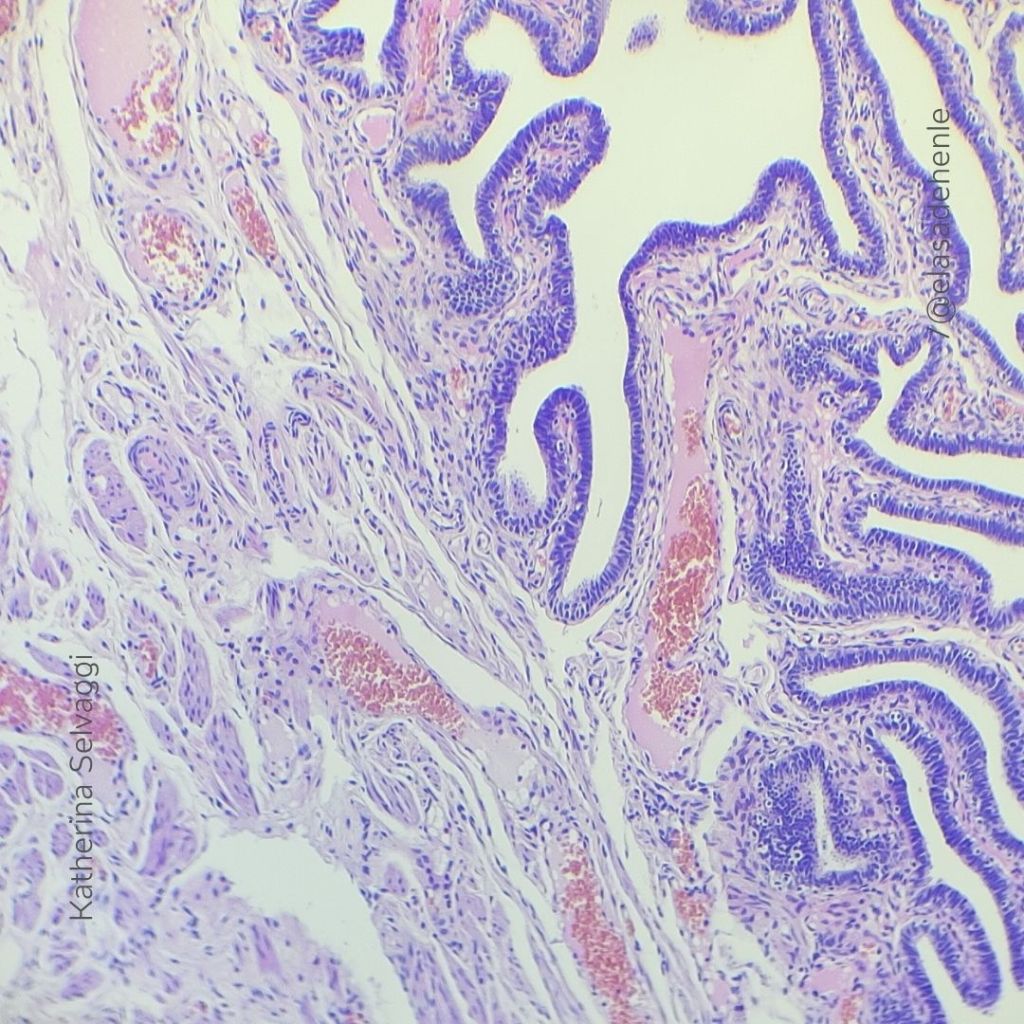

Hematoxilina y eosina

Trompa de Falopio.

COMECA